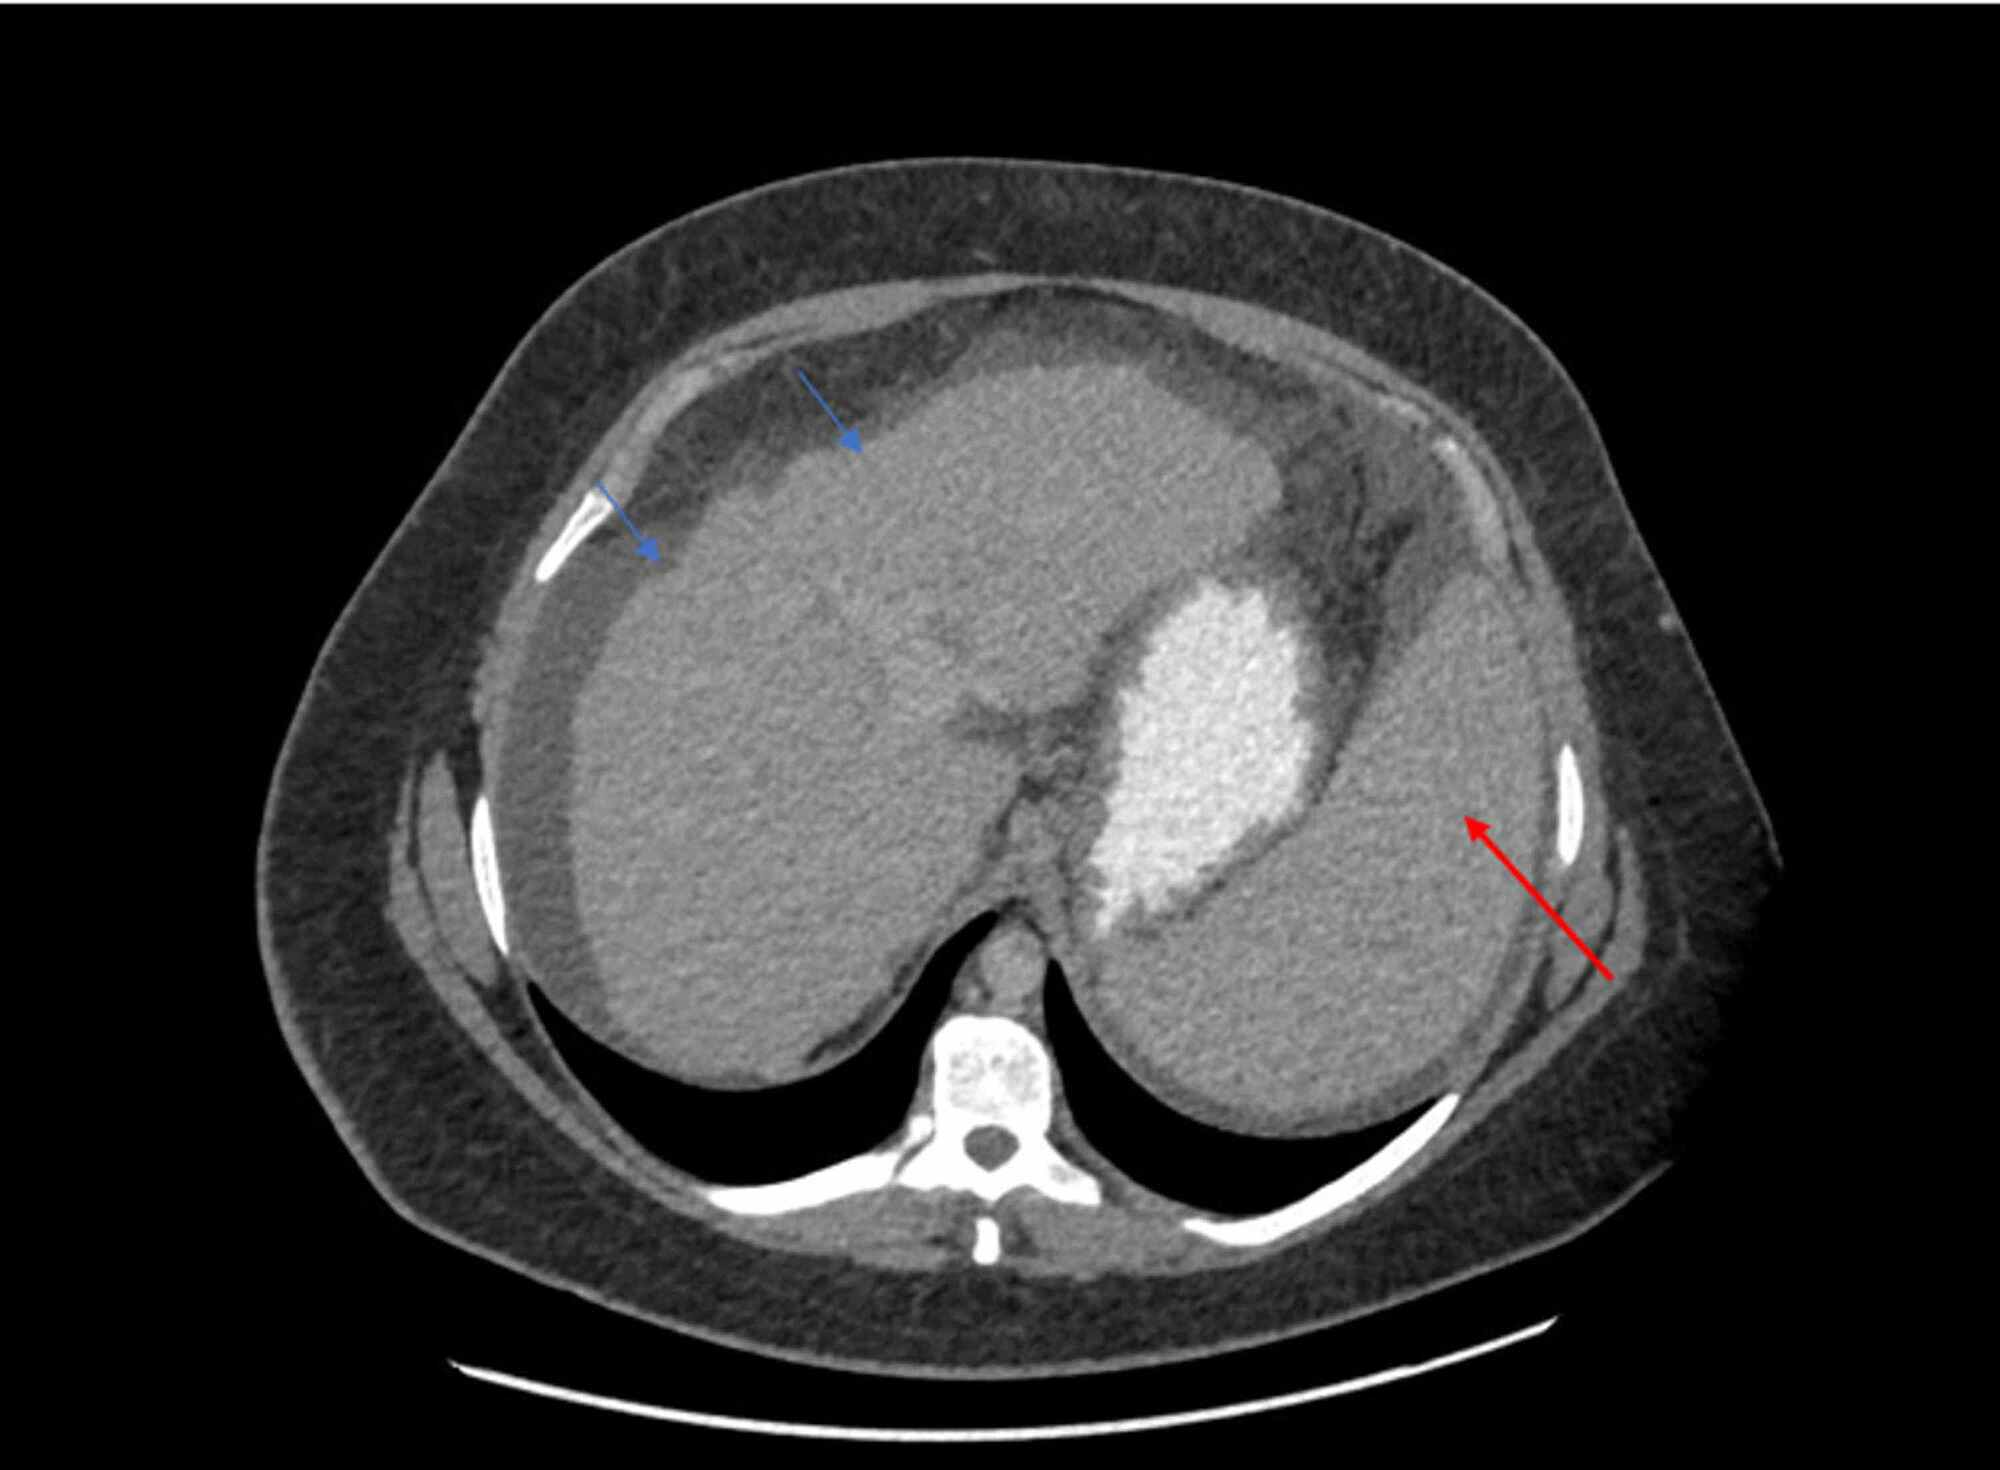

Normal liver and spleen, CT scan Stock Image C014/7032 Science Ct Scan Liver Your doctor may order a combination of tests to. a liver scan is an imaging test to look at your liver and see how well it's working. — there is no single test that can diagnose all liver lesions. learn about the purpose, risks, and preparation of a ct scan of the liver and biliary tract, a. Ct Scan Liver.